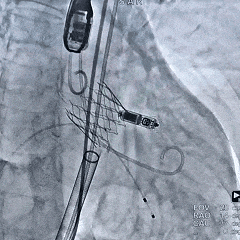

瓣脱钩后造影,瓣膜位置可,无瓣周漏

2025年11月11日,在心外科、心内科、介入导管室、麻醉科、超声科、手术室、体外循环等多学科团队的严密护航下,手术顺利展开,整个操作过程稳、准、快,成功为这一重症患者更换“心门”。术后即刻超声显示:主动脉瓣反流完全消失,新瓣膜工作正常。随着“主阀门”功能的恢复,心脏内部的血流动力学得到整体改善,连带二尖瓣和三尖瓣的反流也显著减轻。看到良好的手术效果,所有团队成员悬着的心也终于落地。更可喜的是,由于手术创伤小,患者在术后当天便顺利拔除了气管插管,第三天转回普通病房,顺利康复,困扰许久的心衰症状得到治愈。